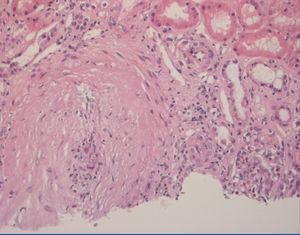

A 70-year-old male with a history of bronchial asthma was admitted due to pulmonary infiltrates, eosinophilia, and MPO-p-ANCA 1:160. The patient was diagnosed with CSS and he was started on 1mg/kg/day prednisone. After 20 days he showed deterioration in renal function, microhaematuria without proteinuria, high blood pressure and elevated p-ANCA 1:1320. A percutaneous renal biopsy was performed, and we observed glomeruli without significant abnormalities and a medium-sized artery with fibrinoid necrosis and transmural infiltration of neutrophils along with intense interstitial lymphoplasmacytic inflammatory infiltrate with abundant eosinophils (Figure 1). Using direct immunofluorescence (DIF) we detected IgG, IgM, C3, C4 and C1q vascular deposits.

Figure 1. First renal biopsy (H-E).